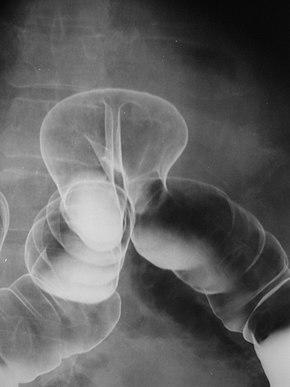

Colonic Herniation 08787.jpg

Radiograph of a barium enema displaying a colonic herniation.

A lower gastrointestinal series is a medical procedure used to examine and diagnose problems with the human colon (large intestine). Radiographs (X-ray pictures) are taken while barium sulfate, a radiocontrast agent, fills the colon via an enema through the rectum.